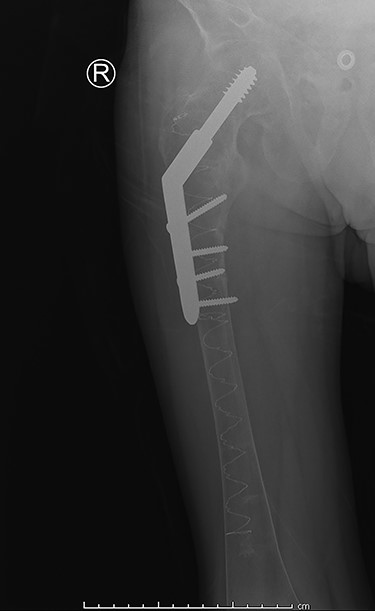

Our patient was discharged from the hospital 14 days after the surgery. The long hospital stay was mostly due to the management of the renal Fanconi syndrome. He was able to mobilize with crutches at time of discharge. The in-hospital stay was without complications. Eight weeks postoperatively our patient returned to our outpatient clinic. Full mobilization was possible and there was a full range of motion. Conventional imaging showed an adequate position of our hybrid osteosynthesis (Fig. 3) and an almost completely healed fracture site.

Post-operative anterior–posterior view: DHS osteosynthesis with intramedullary bone enhancement.